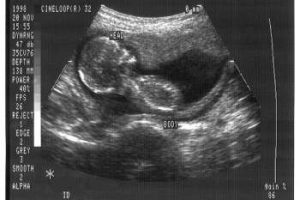

Gov. Kasich signed the state’s Pain-Capable Unborn Child Protection Act on Dec. 13, making Ohio the 18th state since 2010 to enact a ban on abortions performed after 20 weeks of pregnancy. Exceptions would exist for cases of babies conceived through rape or incest, or where the life of the mother is deemed to be at stake.

The science shows that these unborn babies can feel pain and can even survive delivery at around 20 weeks after fertilization, the Charlotte Lozier Institute, the research arm of Susan B. Anthony List, says.

“Fetal surgeons recognize unborn babies as patients,” they stated in a 2015 fact-sheet. “Perinatal medicine now treats unborn babies as young as 16 weeks post-fertilization (18 weeks gestation). Pain medication for unborn patients is routinely administered as standard medical practice.”

And “the leading textbook on clinical anesthesia” notes that babies as young as 18 weeks gestation can have a physiochemical stress response to noxious stimuli,” they added.